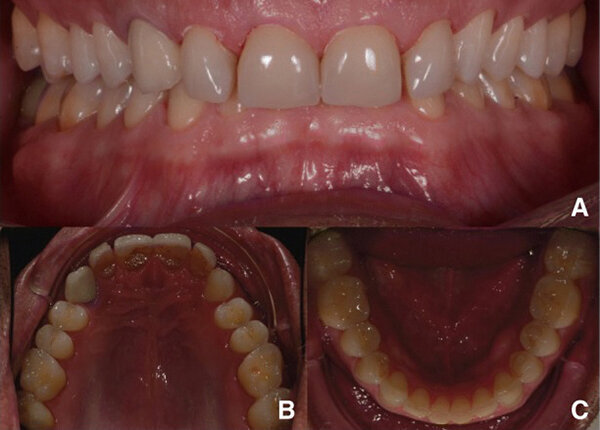

Fig. 14. Fotografías intraorales del tratamiento finalizado. a y b Vista frontal. c Vista oclusal de la mandíbula superior. d Vista oclusal de la mandíbula inferior.

Las coronas (n° 11-13 y 21-23) y las carillas (n° 14-17, 24-27, 31-37 y 41-47) se fijan en los pilares utilizando un adhesivo de resina fotopolimerizable (Futurabond U y Bifix QM, VOCO). Se usó un dispositivo de fotocurado LED de alto rendimiento (Celalux 3, VOCO) para la polimerización (Figs. 11 y 12).

Se retiró el exceso de material de fijación, y la oclusión se adaptó y verificó con la tecnología T-Scan (Tekscan). Se usó una férula de resina acrílica removible para proteger las restauraciones finales. Las restauraciones finales se verifican después de seis meses. Las restauraciones estaban estables y no mostraban signos de fractura (Figs. 13-15). El paciente también informó que ya no sufría dolores de cabeza con la nueva altura de la mordida.